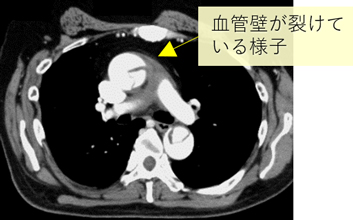

1.大動脈解離ってなに?

大動脈の内側の層(内膜~中膜)が剥がれることを大動脈解離といいます。外側に残ったはがれた壁はとても薄く、ここに強い血圧が生じるため、破れる可能性があります。また薄い壁から血液成分が漏れでていきます。